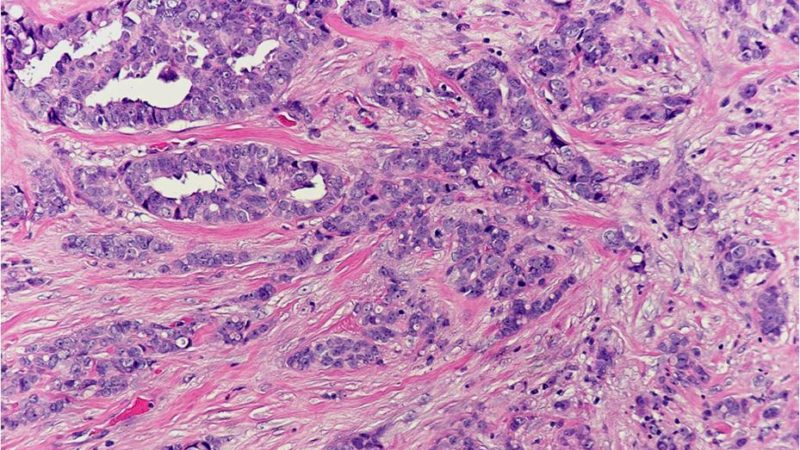

Cancer cells with the ability to invade surrounding tissue and with the potential to metastasize (spread) to lymph nodes and distant organs.

A pattern of growth where the cancer cells grow into (invade) the surrounding tissues (see also infiltrating).

A histologic description of how closely the cancer cells resemble their normal cell of origin. In the breast, the overall grade score is calculated by looking at the mitotic rate, the nuclear grade or atypia, and the degree of gland formation. The final grade will be either grade 1, 2 or 3. In general, a higher tumor grade is associated with more aggressive behavior.

A type of carcinoma (cancer) that arises from glandular cells.